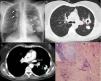

a) Radiografía simple de tórax: múltiples imágenes nodulares en ambos campos pulmonares, algunas cavitadas; b) TC de tórax (ventana parénquima pulmonar): nódulos pulmonares con cavitación central y retracción pleuroparenquimatosa (flecha); c) TC de tórax (ventana mediastino): nódulo cavitado y con calcificación amorfa interna (flecha), y d) Histológicamente se observa una constitución de tejido colágeno denso con microdepósitos de calcio centrales y acúmulos de linfocitos en la zona central y en la periferia (hematoxilina-eosina ×40).

La biopsia transbronquial no fue concluyente, por lo que se realizó biopsia quirúrgica. Macroscópicamente se visualizan al menos 4 nódulos blanquecinos y de consistencia dura con retracción y adherencias pleuropulmonares. El nódulo remitido para estudio histológico está constituido de tejido colágeno denso, con microdepósitos cálcicos centrales y acúmulos de linfocitos (fig. 1d). Los hallazgos fueron compatibles con granuloma hialinizante pulmonar (GHP).

Mujer de 57 años, fumadora, sin otros antecedentes de interés. Acude por disnea de una semana de evolución, tos con expectoración y febrícula. La radiografía de tórax muestra múltiples imágenes nodulares bilaterales, algunas cavitadas (fig. 1a). En la tomografía computarizada (TC) se confirma la presencia de múltiples masas cavitadas en ambos hemitórax, con calcificaciones amorfas (figs. 1b y c). La serología frente a hidatidosis fue negativa, así como el cultivo de micobacterias en medio de Löwenstein de las muestras de esputo y broncoaspirado.